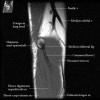

- Sagittal section

1) Biceps Brachii tendon and Brachiallis muscles

2) Radial head for radiographically occult fractures

3) Distal Triceps tendon